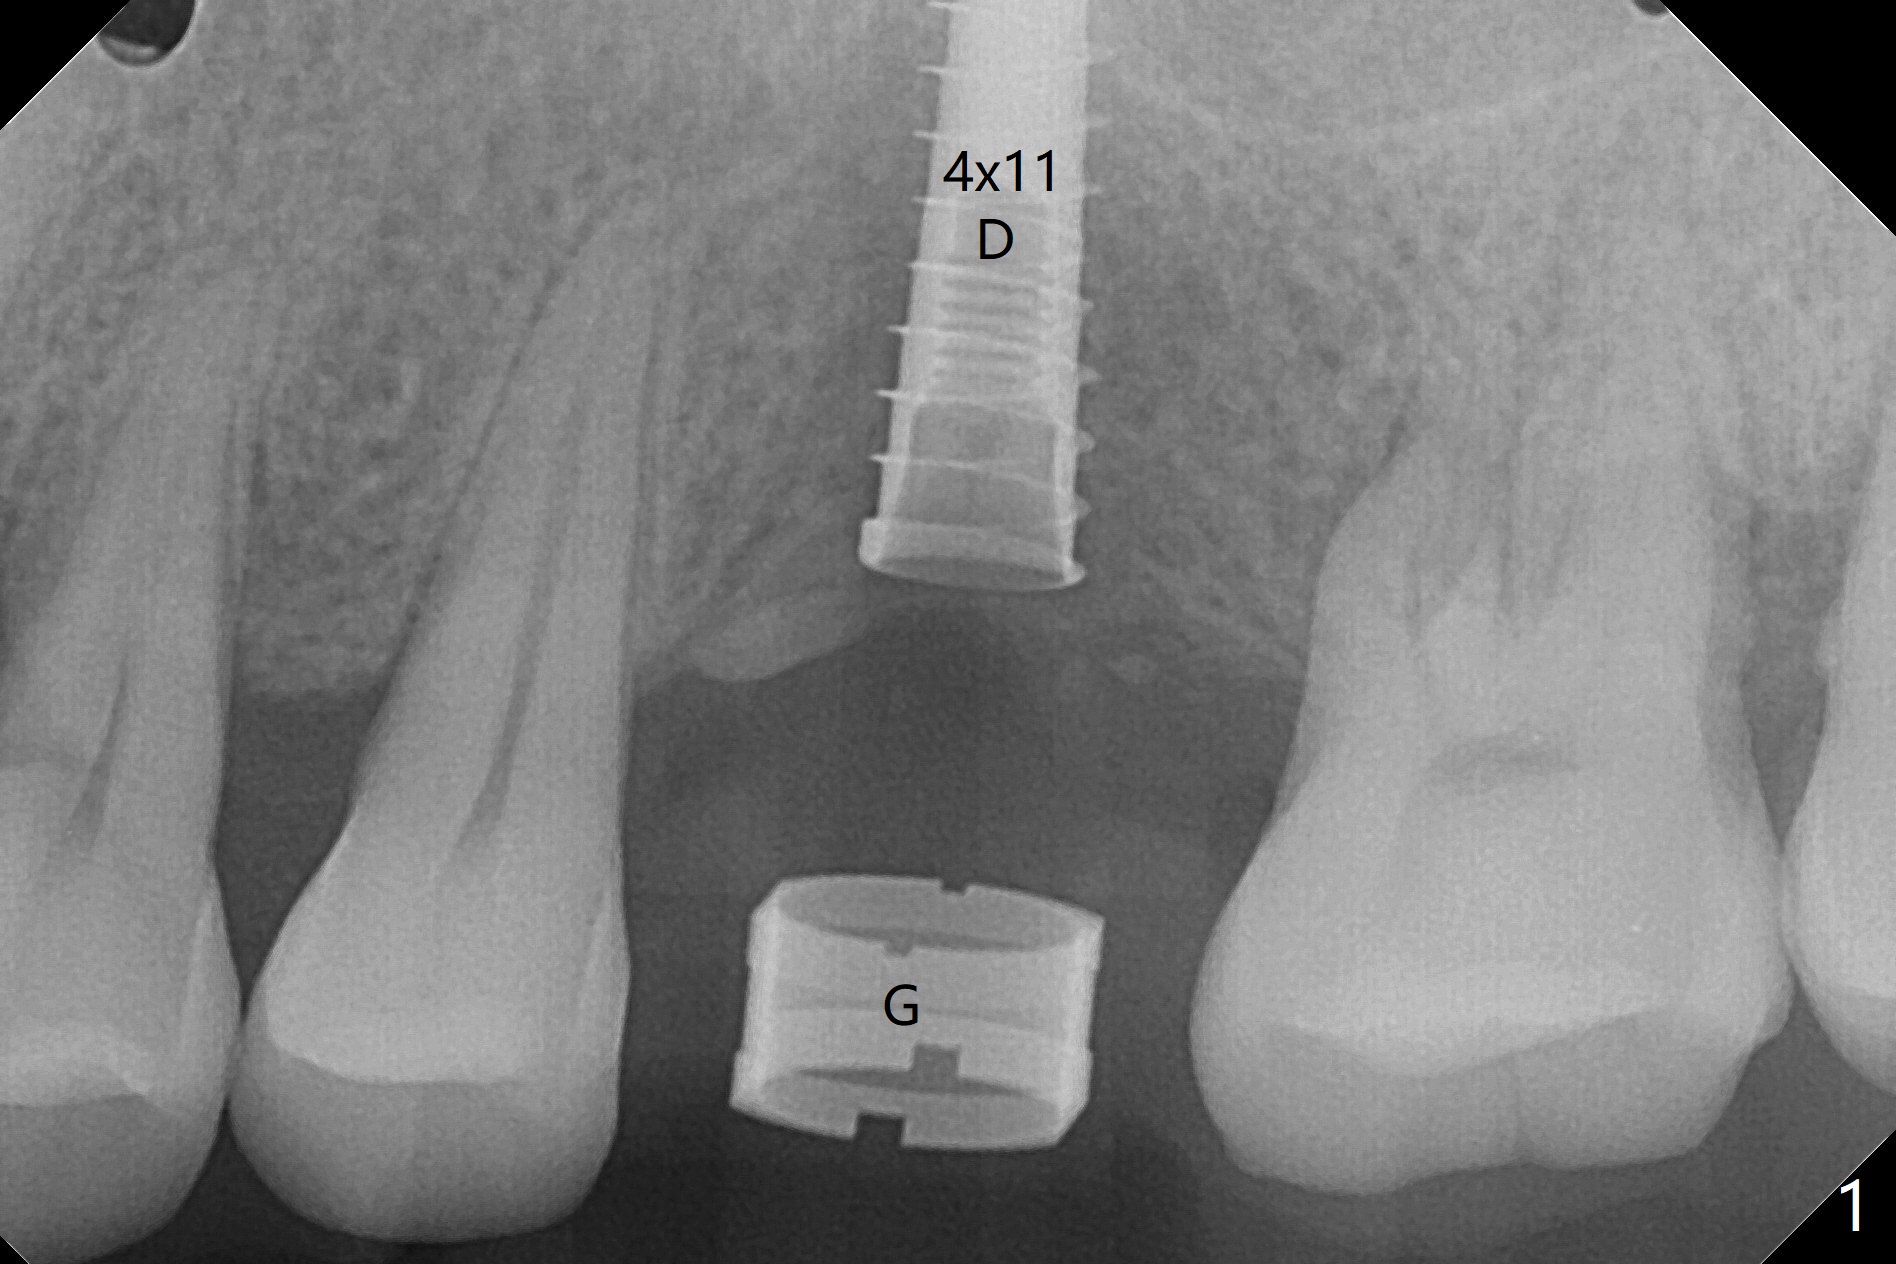

Nearly 4 months post implant exfoliation, the ridge at #14 looks narrow. Incision reveals loss of the palatal plate coronally. The same guide is used to finish osteotomy with modification. There are several points of difference. The 1st one is use of the guide for the complete procedure, including the implant placement so that there would be no apparent trajectory deviation. A bone-level implant is used instead of a tissue-level one. When a 4x11 mm dummy implant is ~1.5 mm shy of the depth (Fig.1 D), the palatal threads are exposed. To reduce further exposure, the final/definitive implant remains 4.0 mm in diameter instead of 4.5 mm as designed, followed by sticky bone, particularly palatal (Fig.2,3 *). In fact the implant is placed deeper than the failed one, relative to the sinus floor (Fig.4 (sinus lift without bone graft)). In fact the implant is placed deeper (Fig.4 (4x11 mm bone-level) than the failed one (Fig.5 (same magnification; 4.5x14 mm tissue-level)), relative to the sinus floor (yellow line).